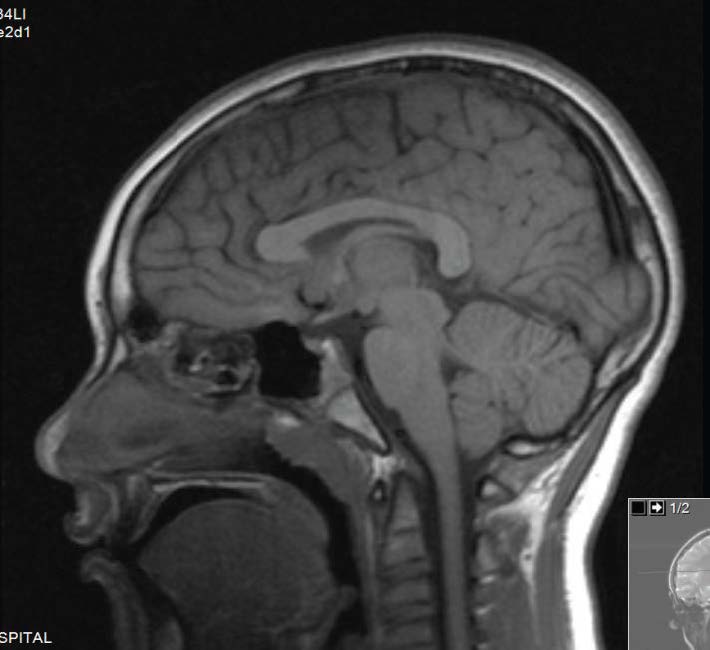

Neha Gupta, MD; Magda Mendez, MD, FAAP; Saurabh Talathi, MD, MPH; Sergey Prokhorov, MD; Maritza Feliz, MD; Naresh Reddivalla, MD

An 8-year-old boy was admitted for evaluation of severe intermittent headache, ataxia, confusion, and slurring of speech.